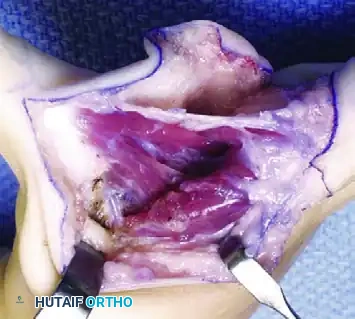

Surgical Technique: The Menelaus Procedure

The procedure requires meticulous soft tissue handling, extensive mobilization of the triceps muscle belly, and careful protection of the ulnar nerve.

Step 1: Exposure and Tendon Harvest

* Position the patient in the lateral decubitus or supine position with the arm draped free over a sterile bolster. Use a sterile tourniquet to optimize the surgical field.

* Make an extensile lateral incision to expose the distal aspect of the triceps muscle, continuing distally to expose the anterior, lateral, and posterior aspects of the proximal ulna.

* Identify the broad triceps insertion on the olecranon.

* Dissect a robust, V-shaped "tongue" of periosteum from the proximal end of the ulna, maintaining its continuity with the distal triceps tendon. This periosteal extension is critical for providing adequate length and a durable tissue interface for the subsequent osseous fixation.

Step 2: Muscle Mobilization and Nerve Protection

* Proceed with proximal dissection of the triceps muscle belly up to the midarm level. Free the muscle from its fascial attachments to the intermuscular septa to ensure maximum excursion.

* Identify, neurolyse, and mobilize the ulnar nerve. The nerve must be protected throughout the procedure, as the proximal mobilization of the triceps can place it under significant traction.

* Perform a posterior capsulotomy of the elbow joint to facilitate unimpeded flexion and to allow the transferred tendon to glide smoothly anteriorly.

Step 3: Tendon Routing and Fixation

* Tubularize (roll) the periosteal tongue and the distal triceps tendon using a running locking suture (e.g., #1 or #2 nonabsorbable braided suture) to create a strong, cylindrical graft.

* Identify the coronoid process of the ulna anteriorly. Using a drill and curettes, create a transosseous tunnel through the coronoid process.

* Pass the tubularized triceps tendon through the coronoid tunnel from anterior to posterior.

Step 4: Tensioning and Closure

* With the elbow held in 120 degrees of flexion and the forearm in neutral rotation, apply maximum physiological tension to the transferred tendon.

* Secure the transfer to the ulna using heavy nonabsorbable sutures, tying them over a bony bridge or utilizing a biotenodesis screw if bone stock permits.

* Deflate the tourniquet, achieve meticulous hemostasis, and close the wound in layers.